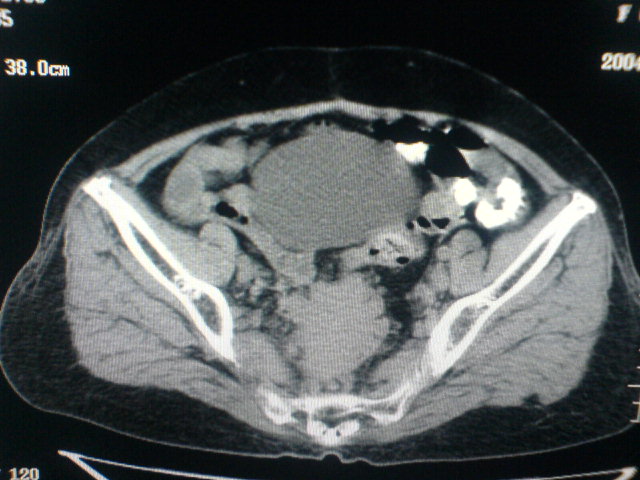

患者为老年女性,肿块最大层面不是位于宫颈,但宫颈偏后方有一囊状低密度影,肿块主要位于乙状结肠及直肠,所以考虑乙状结肠及直肠癌浸犯宫颈可能性大。

患者女性60岁 病史不详

宫颈癌侵犯直肠可能

考虑子宫内膜癌浸犯直肠。

考虑直肠癌侵及宫颈可能;建议增强扫描。

支持考虑宫颈癌上下前后通吃

考虑:直肠及乙状结肠癌侵及宫颈,囊性转移(假性粘液瘤)

支持宫颈癌侵犯直肠。

考虑直肠及乙状结肠癌侵犯邻近结构。